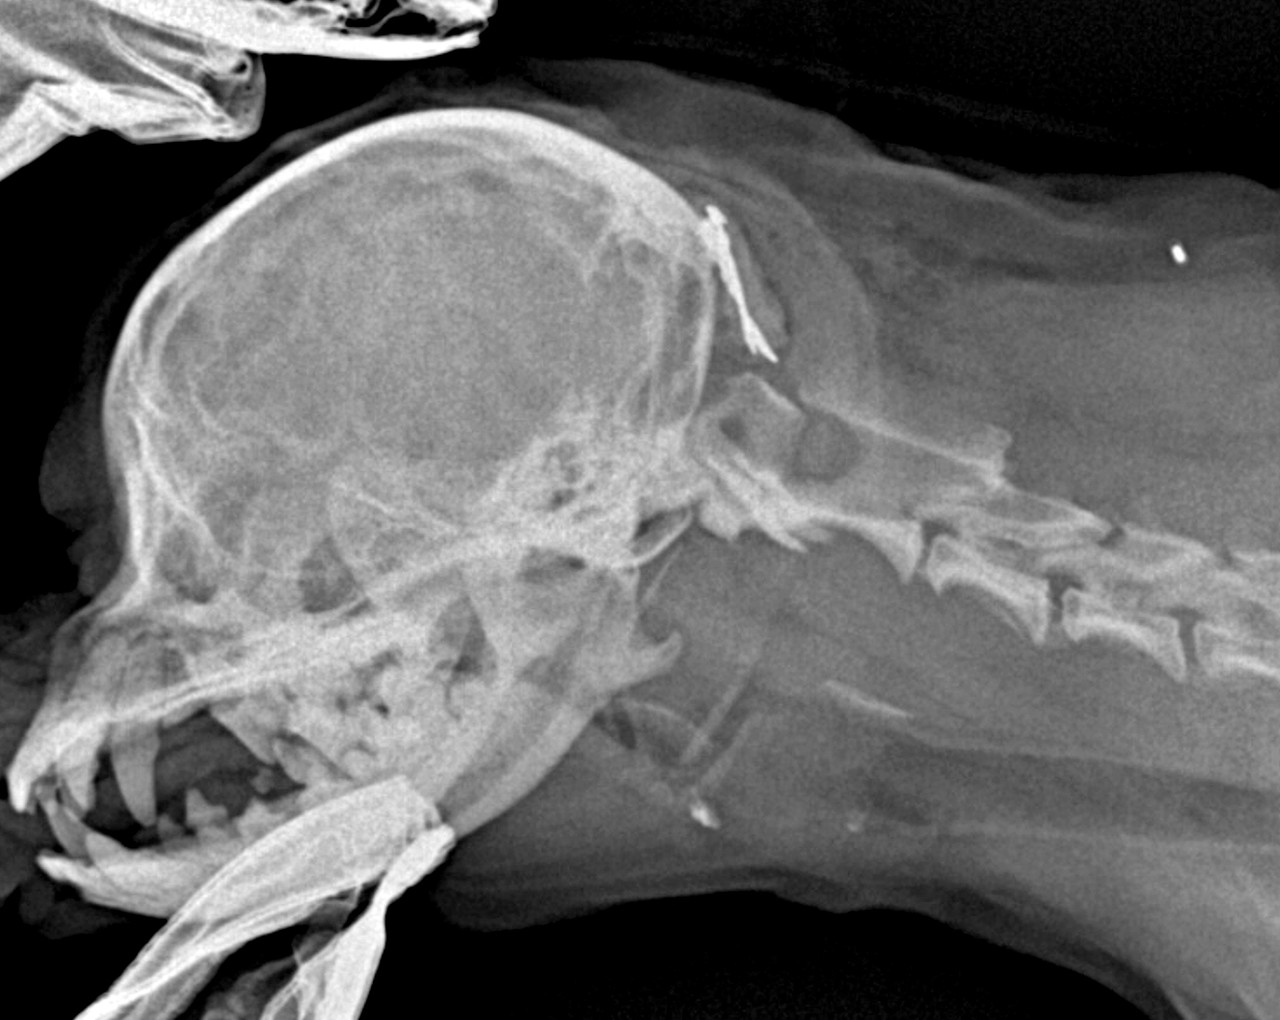

MRI, CT 등 첨단 영상 의료기기를 활용하여 정확하게 진단하고 안전하게 치료하고 있습니다.

1번 경추인 환추와 2번 경추인 축추를 합쳐서 환축추라고 부릅니다.

환축추에 문제가 발생해 불완전한 탈구가 발생하면 척수신경에 영향을 주어 통증 및 사지마비 등이 발생할 수 있습니다.